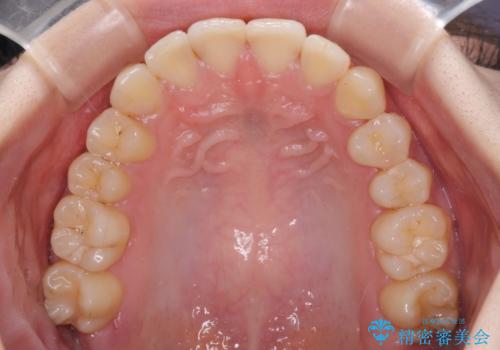

- 上下前歯のデコボコを気にして来院された患者様です。

以前矯正をした後戻りということで、歯列不正はそれほど大きくなかったため、インビザライン・ライトを用いて矯正治療を行うこととしました。

インビザラインは1日に22時間を目安に装着していただきますが、装着時間が十分でないとシミュレーション通りに動かないことがあります。

前歯のデコボコが残っており、シミュレーション通りに動いていない部分がありましたが、再矯正であることやご本人の満足いくところまでデコボコが改善されたとのことで、治療を終了することとしました。